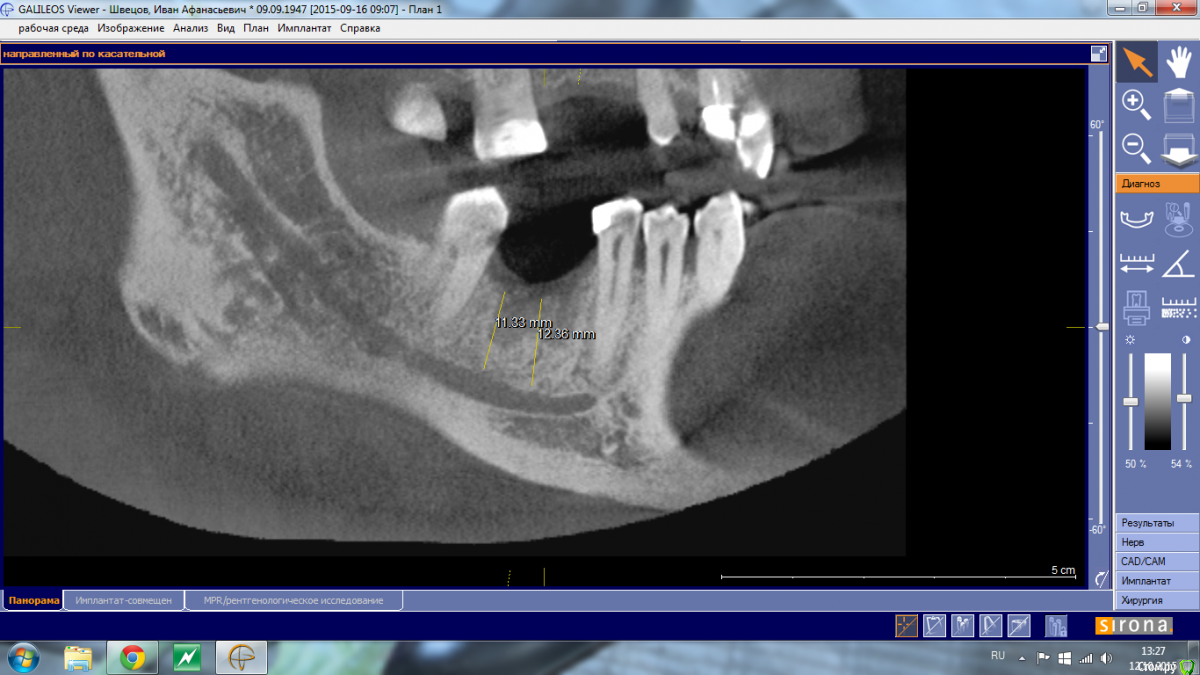

Shakirbura Опубликовано 12 октября, 2015 Автор Поделиться Опубликовано 12 октября, 2015 Снимок до имплантации.Сверло уперлось в 8-9 мм, что для меня было неожиданностью Ссылка на комментарий

АнтонТЛТ Опубликовано 13 октября, 2015 Поделиться Опубликовано 13 октября, 2015 Снимок до имплантации.Сверло уперлось в 8-9 мм, что для меня было неожиданностьюСкорее всего уперлись в подъязычное поднутрение, резцы с парестезией? 2 Ссылка на комментарий

Shakirbura Опубликовано 13 октября, 2015 Автор Поделиться Опубликовано 13 октября, 2015 Скорее всего уперлись в подъязычное поднутрение, резцы с парестезией?Семент от места имплантации до центра с парестезией. Имплантацию проводил под инфильтрационной анестезией, в момент проваливания пациент не сильно отреагировал. Говорит, что "как будто губу чем то задели". Ссылка на комментарий

АнтонТЛТ Опубликовано 13 октября, 2015 Поделиться Опубликовано 13 октября, 2015 Давайте контрольный снимок, если имплантат далеко от канала, то скорее всего травма + гематома (само пройдет), если имплантат в канале, то вынимать. 3 Ссылка на комментарий